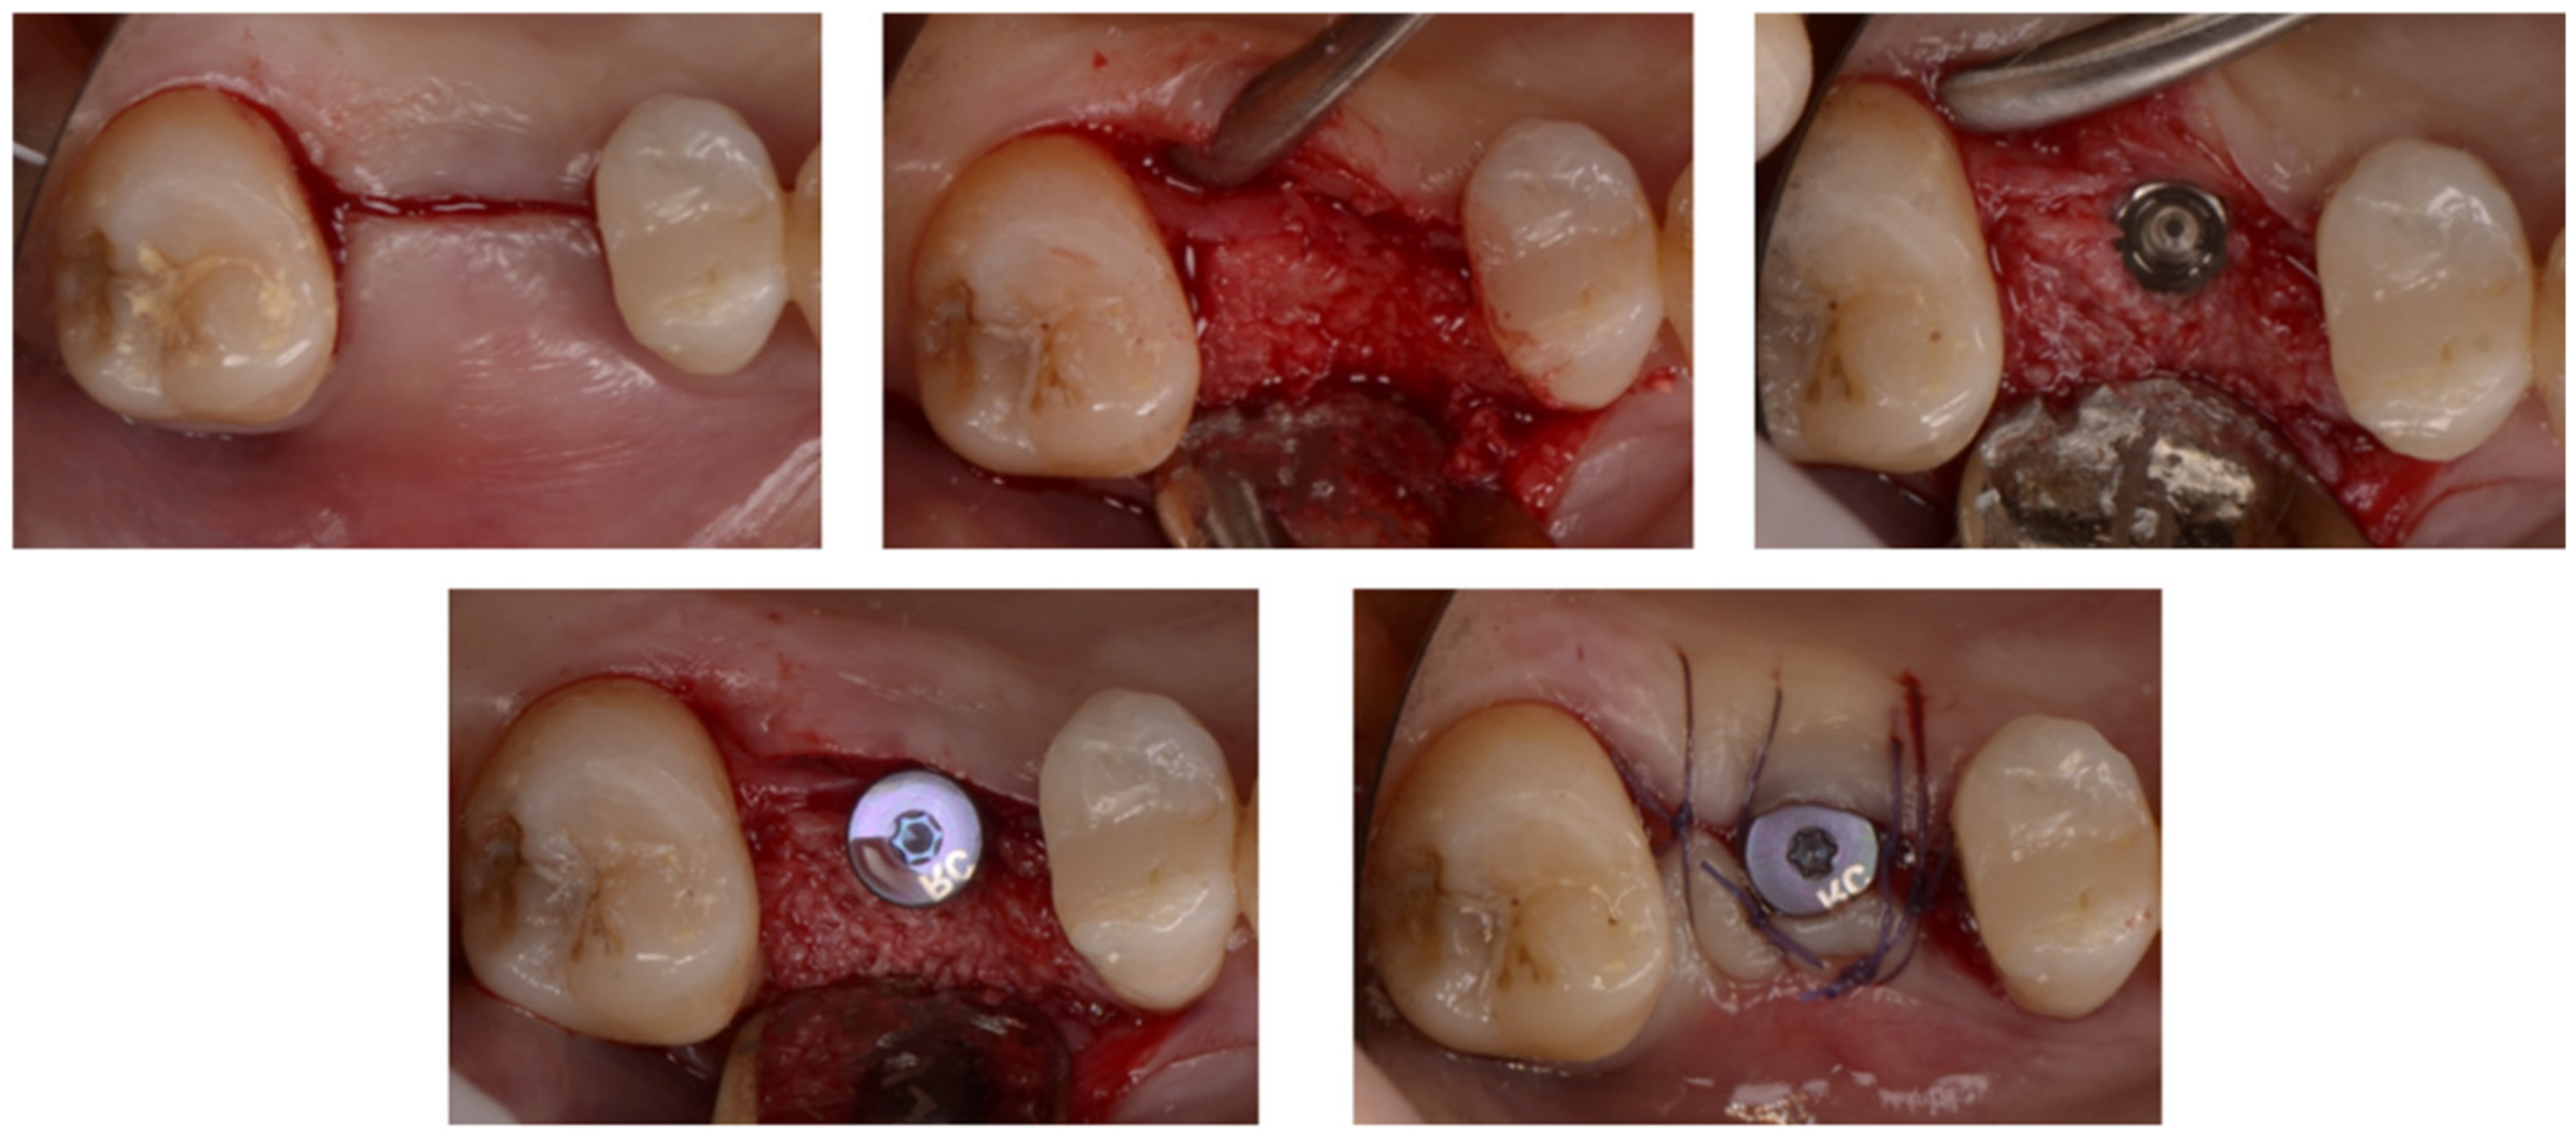

A 43-year-old male patient had a motorcycle accident and traumatically lost teeth 11 and 12. After a period of soft tissue healing the area was operated on in order to place two dental implants to replace the missing teeth (Figure 13 and Figure 14).

Figure 13.

The edentulous area showed some healing at the site of 12 but still a deep dehiscence on 11.

Figure 14.

Two implants in place of the one on 11 with several threads exposed.

The site of 12 presented a very thin but visible buccal plate, while 11 had most of the buccal coronal aspect of the implant exposed. Some small holes were drilled into the buccal plate to produce some bleeding and with cells from the marrow spaces, while the area was augmented with a mix of autogenous bone scraped from the ramus and a collagenated xenograft. A bone lamina was cut and shaped in order to cover the graft and produce some horizontal and vertical augmentation of the area (Figure 15). We can see that some bone loss to the distal of 21 was also evident. Two pins were placed to the buccal apical aspect of the lamina to keep it firmly in place.

Figure 15.

The bone lamina stabilized to protect the two implants.